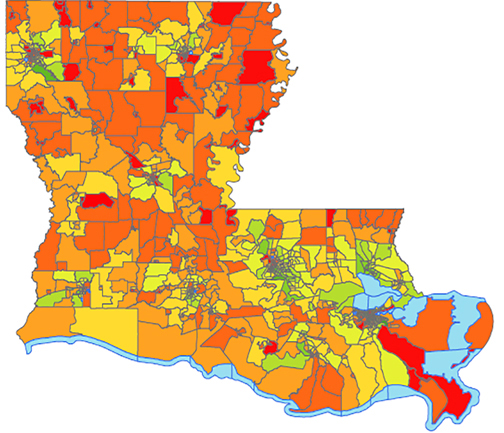

LSU Health New Orleans LA Tumor Registry Releases 6th Census Tract Cancer Incidence Report

LSU Health New Orleans Louisiana Tumor Registry (LTR) has published the sixth report of statewide cancer incidence rates by census tract. The publication, which reports 2010-2019 combined cancer incidence data, found that 81% of the census tracts in Louisiana met publication criteria for all cancers combined. More

LSU Health New Orleans LA Tumor Registry Releases 5th Census Tract Cancer Incidence Report

LSU Health New Orleans Louisiana Tumor Registry (LTR) has published the fifth report of statewide cancer incidence rates by census tract. The publication, which reports 2009-2018 combined cancer incidence data, found that 81% of the census tracts in Louisiana met publication criteria for all cancers combined. For specific cancer types, fewer census tracts met the criteria. For the Louisiana census tracts meeting the criteria, the incidence rates for all cancers combined and for specific cancer types were compared with the corresponding rates for the entire state. More